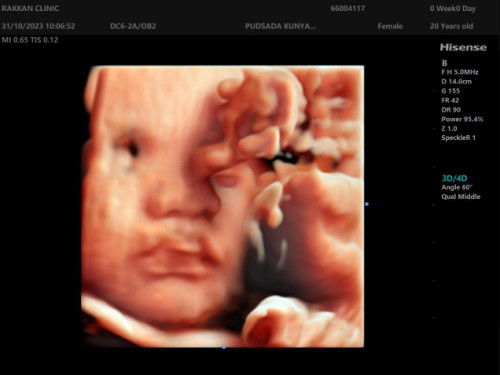

แบบนี้เรียกปากแหว่งไหมคะ ?

คุณหมอพูดเหมือนจะให้แม่เครียด(ไม่ใช่หมอสูนติเฉพาะทาง ฝากคลินิกทั่วไป) เราก็เคยตรวจจากคลินิกเก่ามาละนะ หมอว่าปกติ ตอนนี้32week ซาวด์4มิติที่ผ่านมาน้องก็ปากปกติ ทำไมรอบนี้ทำปากแบบนี้อะลูก แต่ก็แอบเอ็นดูปากน้อง😄